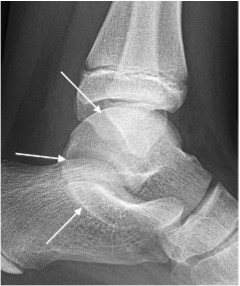

Anterior impingement

- Osseous spurs arising from anterior distal tibia and dorsal talar neck

- Corresponding ‘Divot’ sign may be seen in talar neck

- “Footballer’s ankle” is anterior impingement caused by repetitive micro-trauma

Anterior impingement with anterior distal tibial osseous spur (arrow)